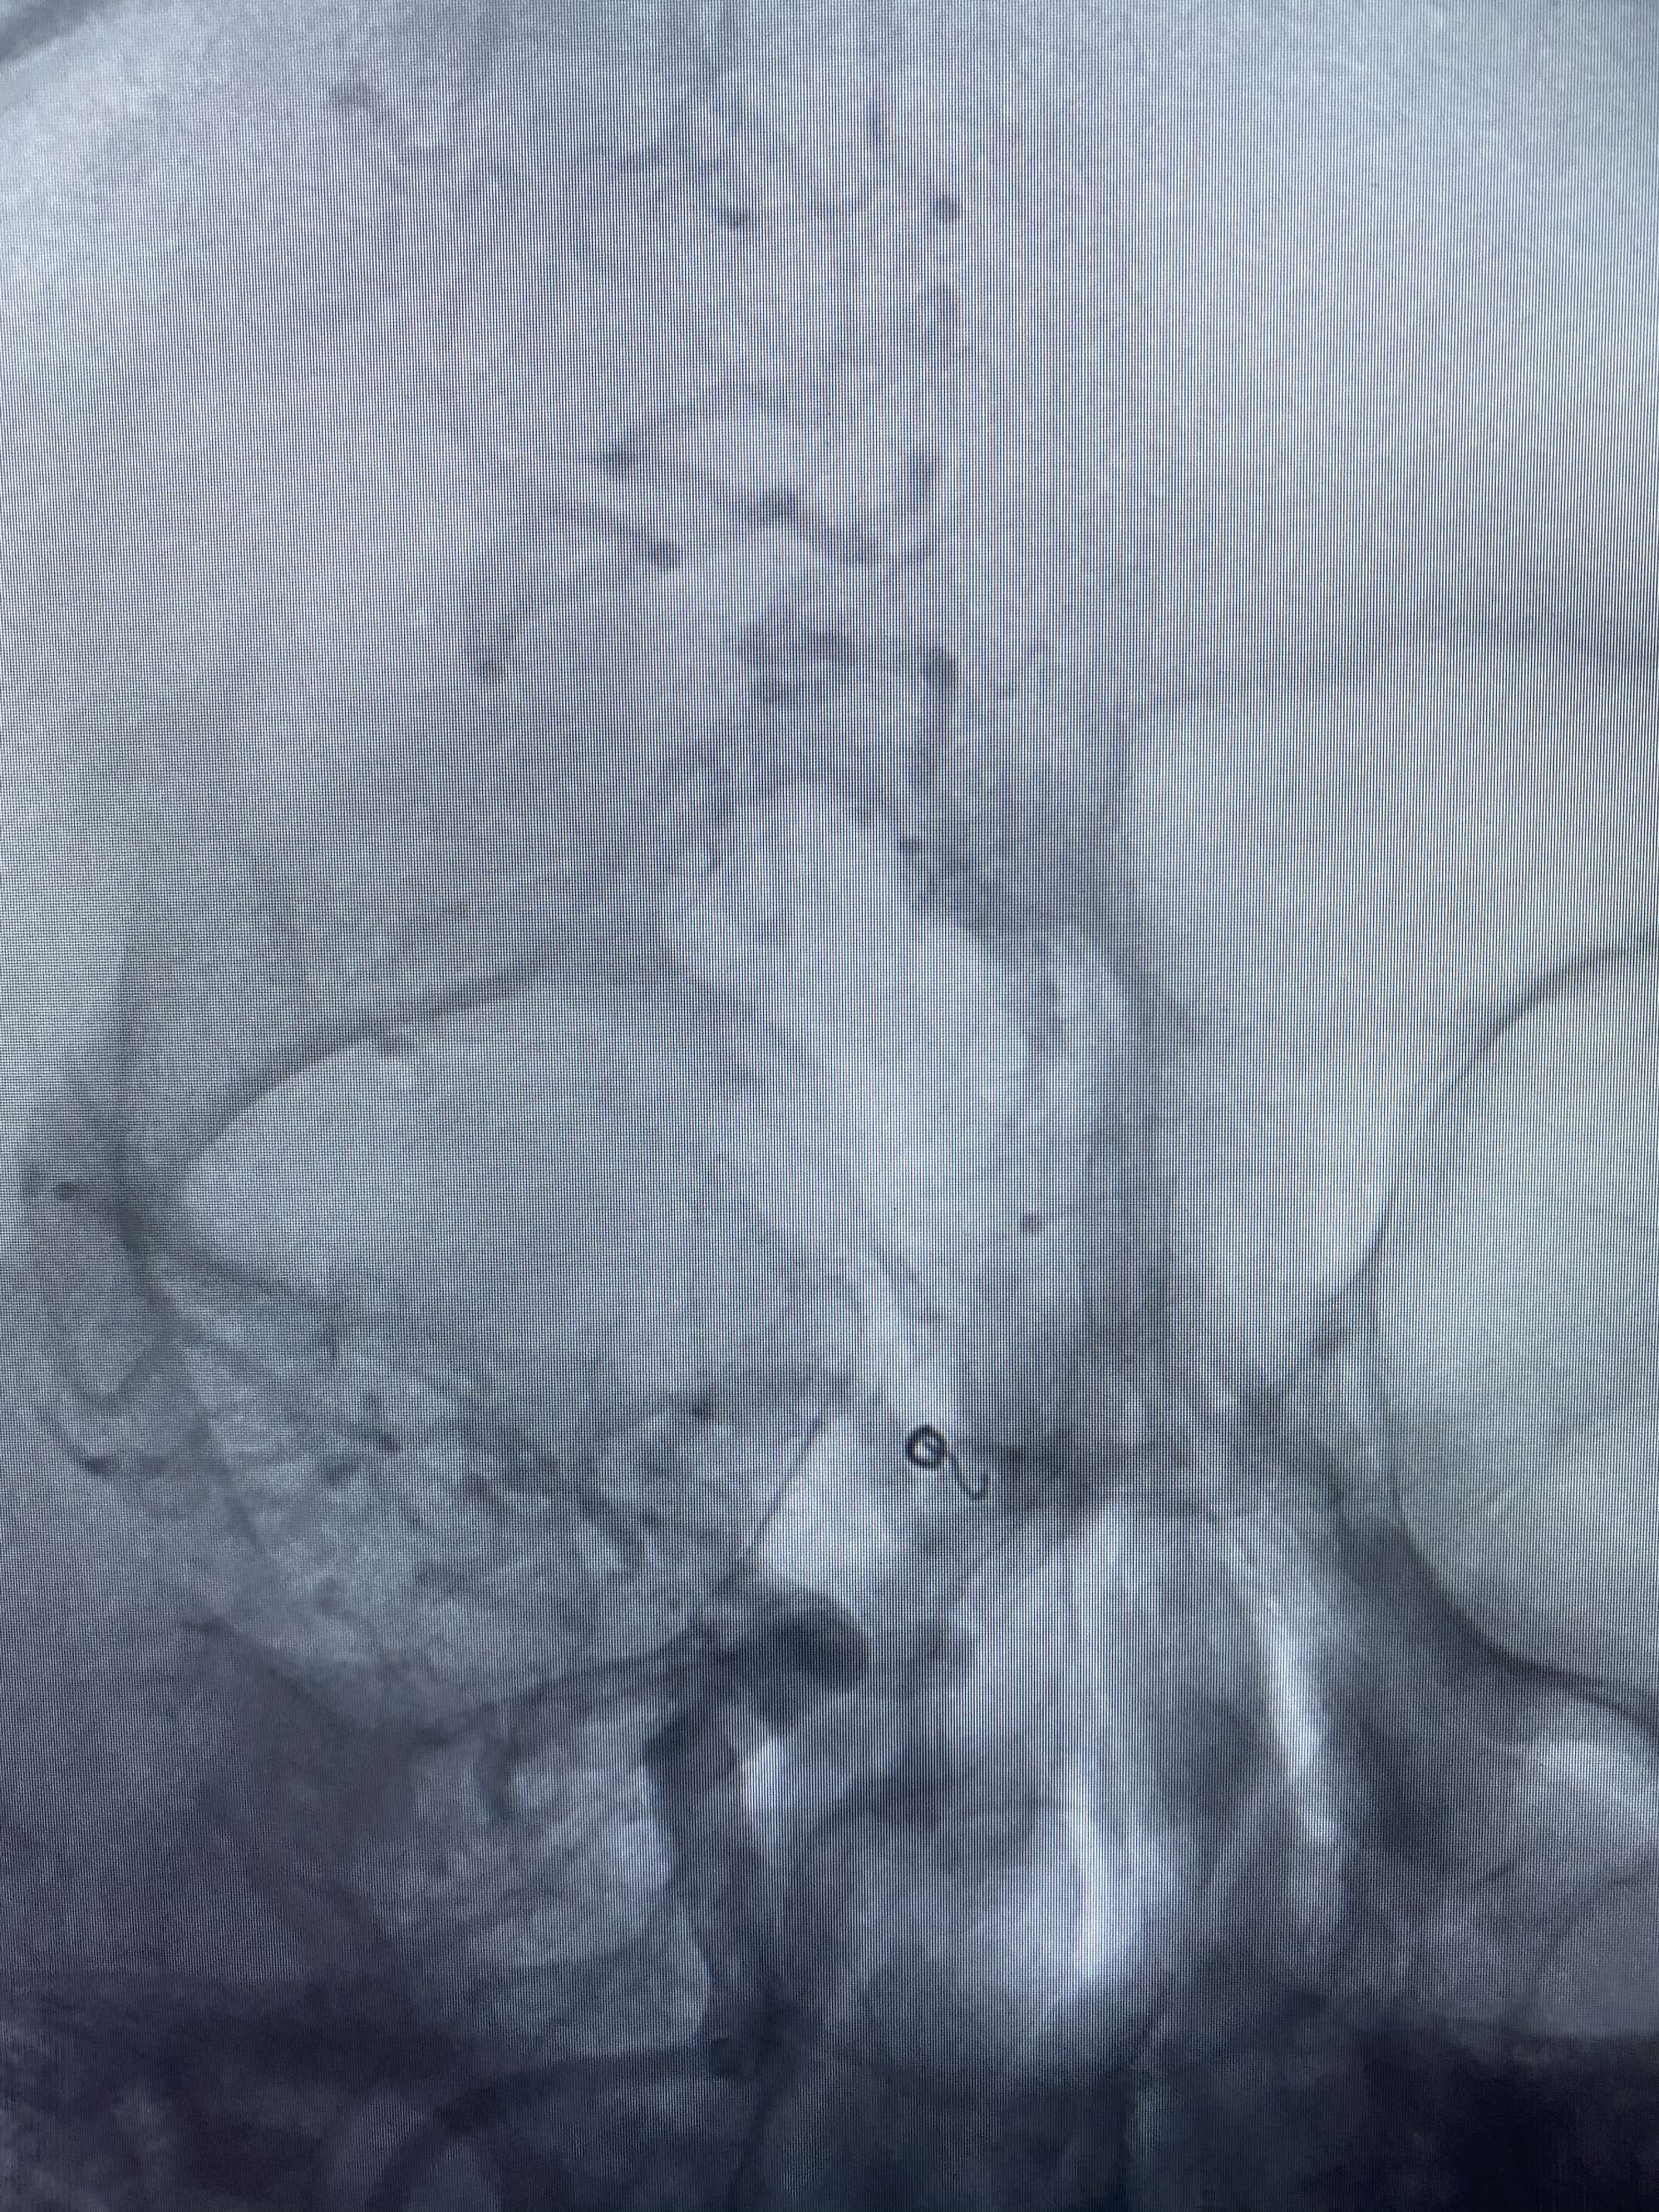

MLS,M79Y,sah,双侧MCA烟雾病,Heubner返动脉瘤,前交通段开窗,细支发出Heubner返动脉,瘤颈细长,瘤颈口比微导管细,弹簧圈2mmx3cm“隔山打牛”填塞治愈,Heubner返动脉保留。

该患者术后2天观察神志清楚,四肢活动正常。